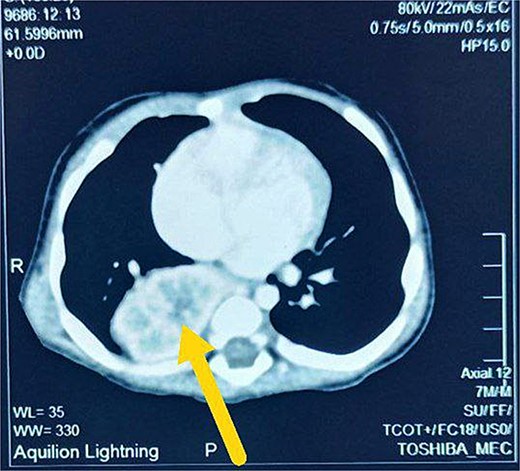

A 7-month-old infant with recurrent hospital admissions for shortness of breath during breastfeeding and recurrent chest infections since birth. He is the fourth child of a mother who had a normal pregnancy and received good antenatal care. Despite a full-term delivery with normal amniotic fluid levels and immediate postnatal crying and passage of meconium, the infant displayed delayed developmental milestones, failure to thrive, and breast milk refusal. Physical examination revealed signs of respiratory distress, including intercostal retractions and diminished right-sided breath sounds. A computed tomography (CT) scan of the chest revealed the right kidney located in the right thoracic cavity, consistent with an intrathoracic kidney (Fig. 1). The presence of a natural opening through which the ureter traversed the diaphragm supported this diagnosis. A mass lateral to the kidney was suspected to be a sequestrated lung lobe. Laboratory investigations returned within normal limits. Differential diagnoses considered congenital diaphragmatic hernia and diaphragmatic eventration. Subsequent thoracotomy revealed an intact right lung, with the ectopic kidney’s Gerota’s fascia adhering to the collapsed lower lobe (Figs 2–4). Sequestration vessels were ligated, and the lung lobe was successfully released from the kidney (Figs 5–7). The kidney remained within the thoracic cavity, and the lower lobe was re-expanded. Postoperative management included hemostasis assurance and chest tube insertion, with no immediate complications noted.

The patient’s clinical history of repeated respiratory distress and chest infections since birth, along with failure to thrive, indicated a serious underlying condition. The initial differential diagnoses included typical pediatric respiratory illnesses; however, the persistence of symptoms despite treatment necessitated additional inquiry. Imaging examinations, particularly a CT scan, revealed the right kidney in the thoracic cavity, next to a mass thought to be a sequestrated lung lobe. The diagnosis of an intrathoracic kidney was supported by the existence of natural holes through which the ureter passed into the thoracic cavity.

The abnormal ascent of the kidney during fetal development is often responsible for intrathoracic kidney formation [13]. Unlike congenital diaphragmatic hernia, which occurs when abdominal contents herniate into the thoracic cavity through a diaphragmatic defect, the intrathoracic kidney typically has a structurally intact diaphragm, but with a natural or unusual opening allowing the ureter to pass through [14]. In this case, the CT results and surgical findings confirmed the diagnosis of an intrathoracic kidney without diaphragmatic hernia, highlighting the rarity of this presentation.